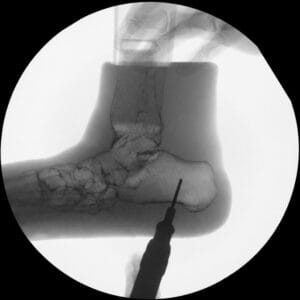

| Pathology | Pes Cavus |

| Procedure | Cole Osteotomy, Dwyer, Lateralizing Calcaneal Osteotomy, Metatarsal Dorsiflexion Osteotomy |

| Area | Midfoot |

Pes Cavus – Bone Model